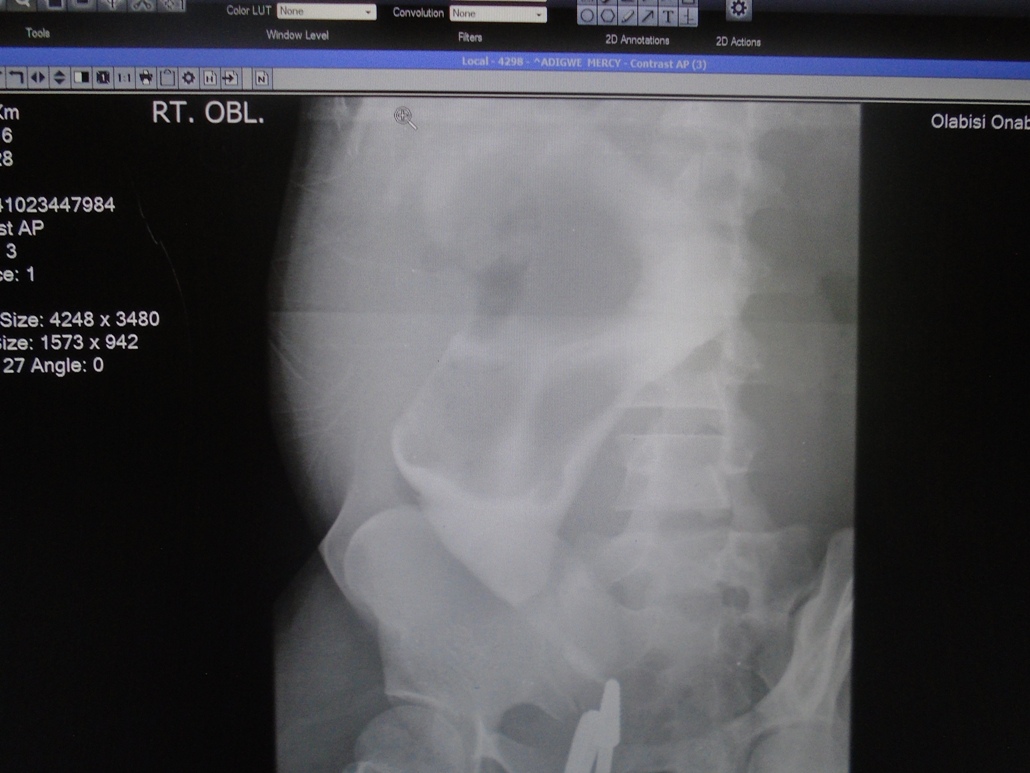

Background: Infertility is a relatively common health challenge in the society with social and psychological consequences. Hysterosalpingogram (HSG) is traditionally used to ascertain some of the causes of infertility. The use of ionizing radiation and contrast media injection with the possibility of complications, make new imaging modalities preferable, especially when in-vitro fertilization is being considered as a management option.

Objective: To describe the pattern of the cervical, uterine, tubal and adnexial abnormalities causing infertility as detected by HSG in a tertiary health care institution, and demonstrate the prospects of retaining Hysterosalpingography in the investigation of female infertility.

Methods: The HSG and reports of 124 patients referred to the Radiology Department of a tertiary health facility between January, 2013 and June, 2014, at a tertiary healthcare institution, were reviewed for abnormalities in the cervix, uterus, the fallopian tubes and adnexial structures.

Results: Secondary infertility was the commonest indication for the procedure among in 66 of the 124 HSG reviewed. Pathologies in the cervix were found in 66 (51.6%) cases, of which the most frequent abnormality was cervical fibrosis in 59.4% (36/66) cases.  Uterine abnormalities were found in 71.7% (89/124) cases, with uterine fibroid occurring in 82% (73/89) of these cases. Pathologies in the Fallopian tube occurred in 68 (54.8%) cases, with bilaterally blocked tubes occurring most frequently in 32.4% (22/68). Twenty-seven of the 68 cases (39.7%) with tubal abnormalities were aged 20-29 years.

Conclusion:  Secondary infertility was the commonest indication for HSG in the study, while uterine fibroid, cervical fibrosis and bilaterally blocked tubes were the most prominent findings in descending order of frequency. Therefore, caution should be exercised in managing pelvic infections, inflammations, diagnostic dilation and curettage and post-abortal and post-surgical periods in order to reduce the risk of fibrosis.